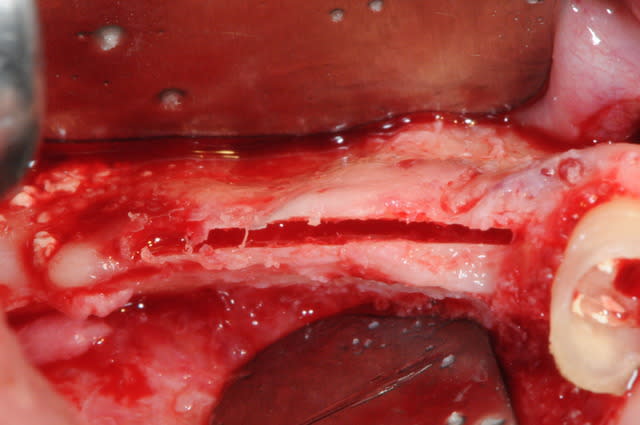

aspect des crêtes et début du sinus lift.

l'os était tellement fin qu'il n'y avait presque pas besoin de la piezo.